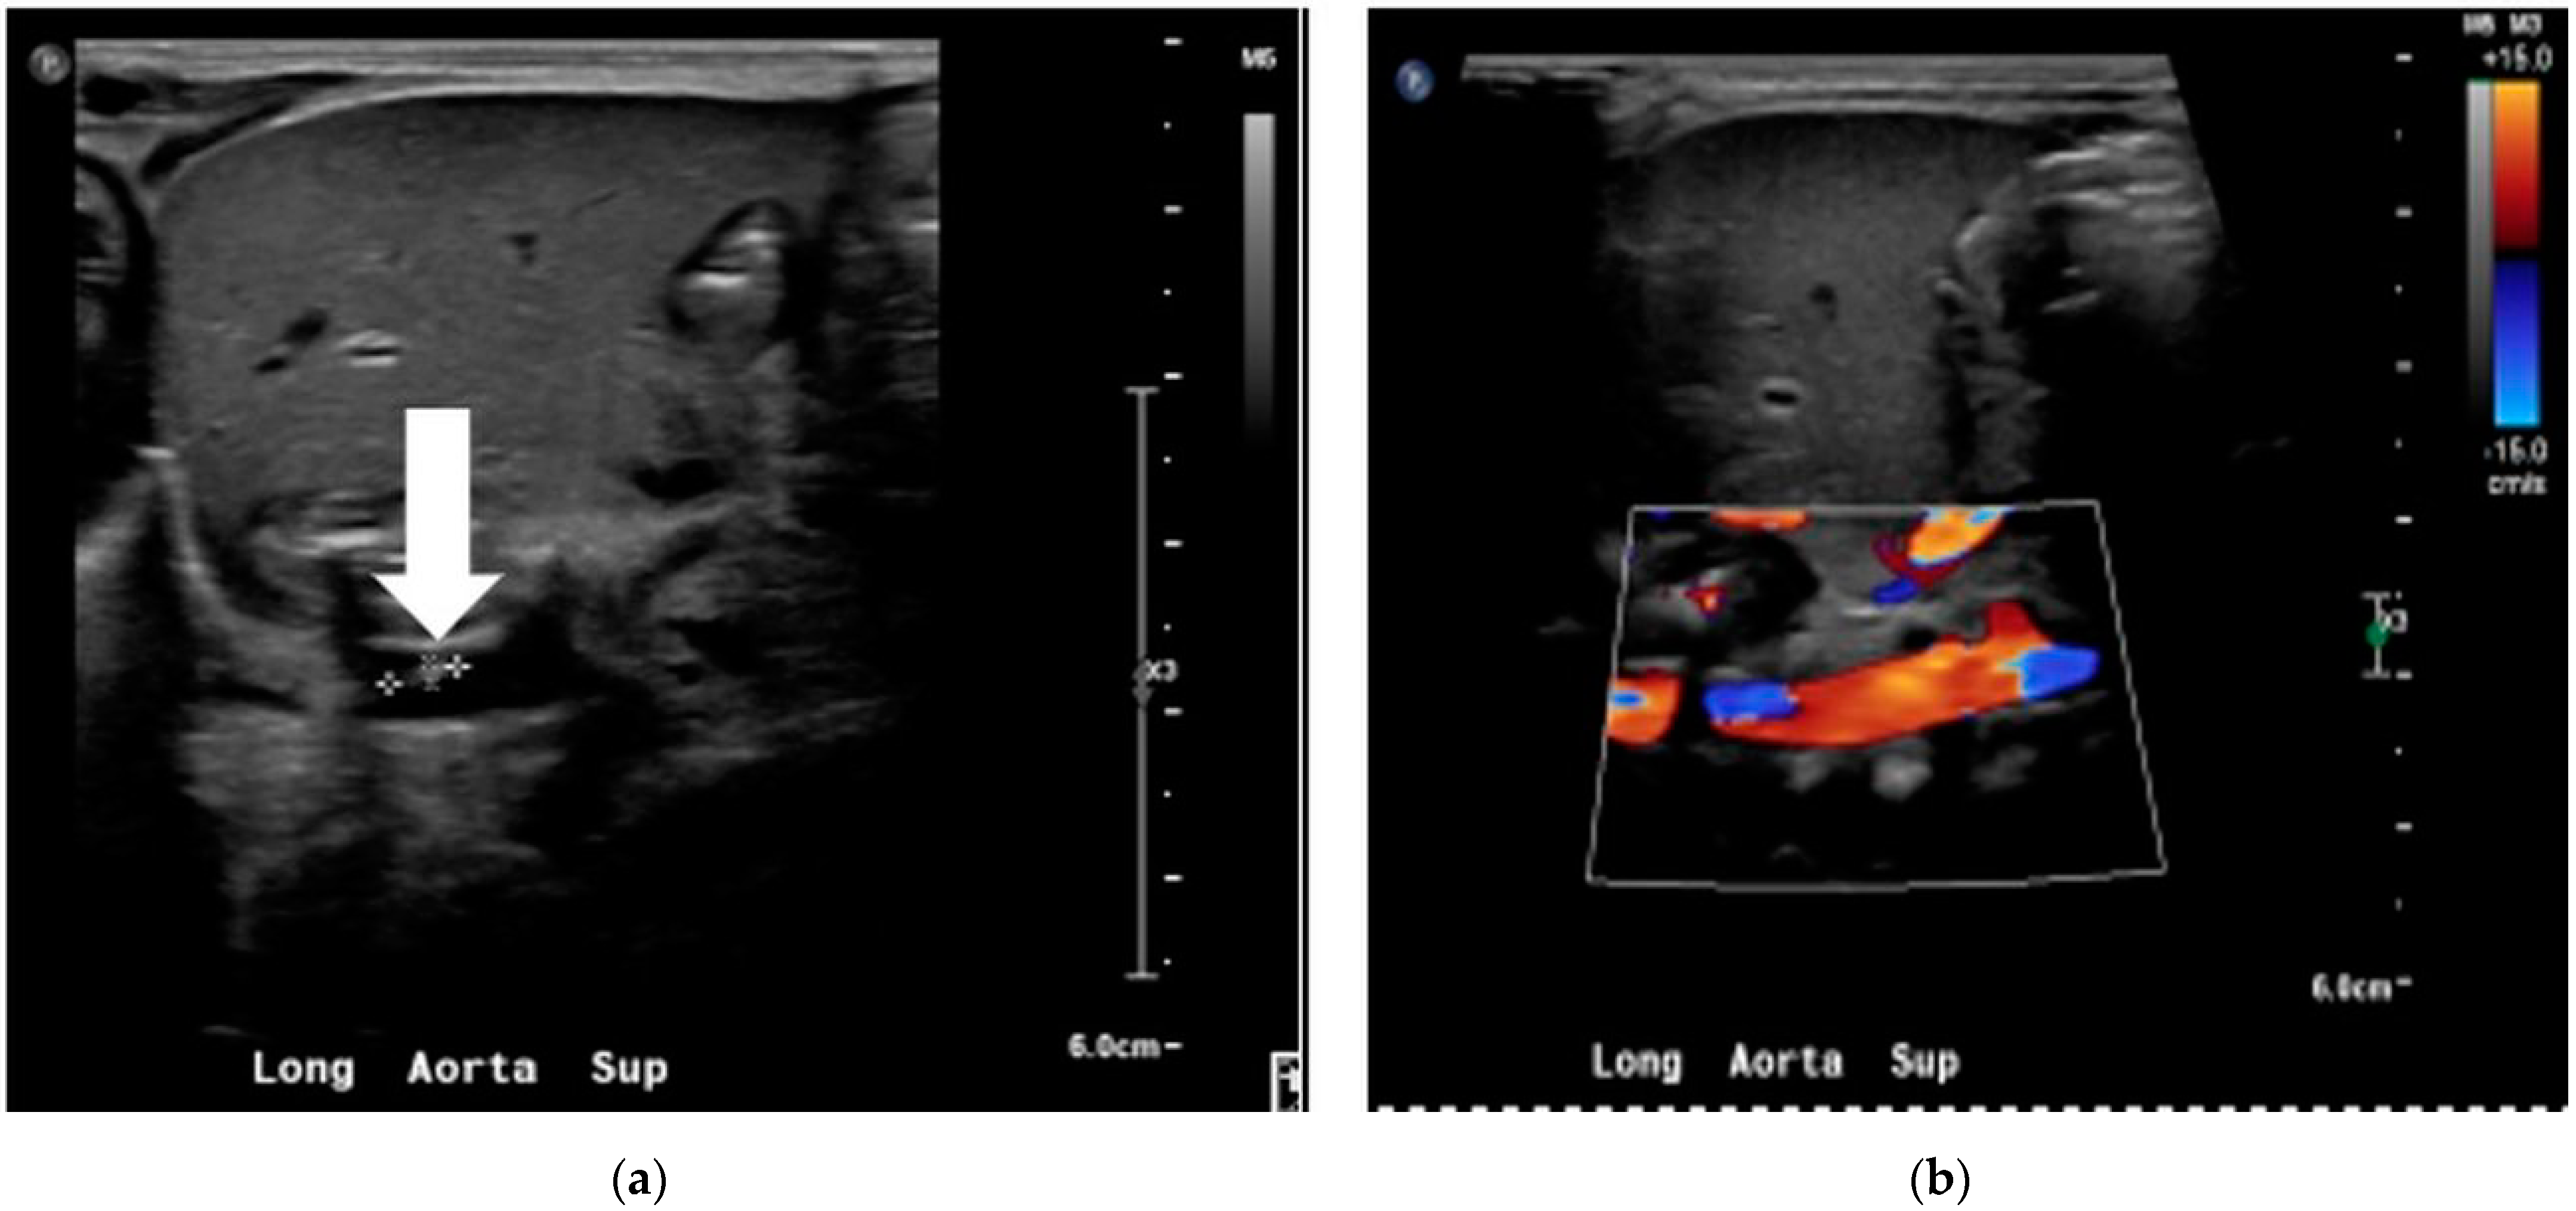

We researched further to find an occult focus because of persistent bacteremia. Transthoracic echocardiogram, abdominal ultrasound, and head sonogram were normal. The aortic Doppler study revealed a non-occlusive thrombus (4 × 1 × 1.5 mm) in the infrarenal portion of the abdominal aorta (see Figure 1).

We consulted subspecialists from pediatric infectious disease and hematology. The aortic thrombus, probably from UAC placement, was considered to be the infective focus responsible for the persistent bacteremia, and the infant was treated with a 6-week course of vancomycin. He was also started on enoxaparin, and the thrombus was followed with serial aortic doppler imaging.

The infant completed 6 weeks of vancomycin therapy and completed 4 weeks of enoxaparin therapy without complication. Follow-up aortic sonogram with dopplers showed a decrease in the size of the thrombus. As a result, the infant was discharged home with multispecialty outpatient follow-up. Figure 2 summarizes the timeline of the events described above.

Figure 1. Aortic doppler study showing the non-occlusive thrombus in the grayscale (a) and color doppler (b).